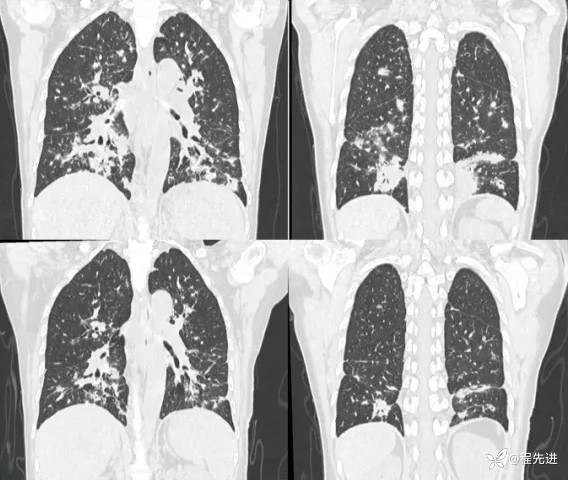

静滴激素、丙种球蛋白及环磷酰胺治疗26天后(上排治疗前,下排治疗后):